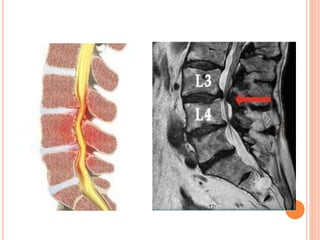

ESTENOSIS DEL CANAL LUMBAR

 Las displasias óseas afectan a los huesos

largos y al mismo tiempo al tamaño de los

cuerpos vertebrales y al diámetro de los

arcos posteriores vertebrales y del agujero

occipital, afectando a veces estructuras

neurológicas adyacentes.

ESTENOSIS DEL CANALLUMBAR  Las displasias óseas afectan a los huesos largos y al mismo tiempo al tamaño de los cuerpos vertebrales y al diámetro de los arcos posteriores vertebrales y del agujero occipital, afectando a veces estructuras neurológicas adyacentes.